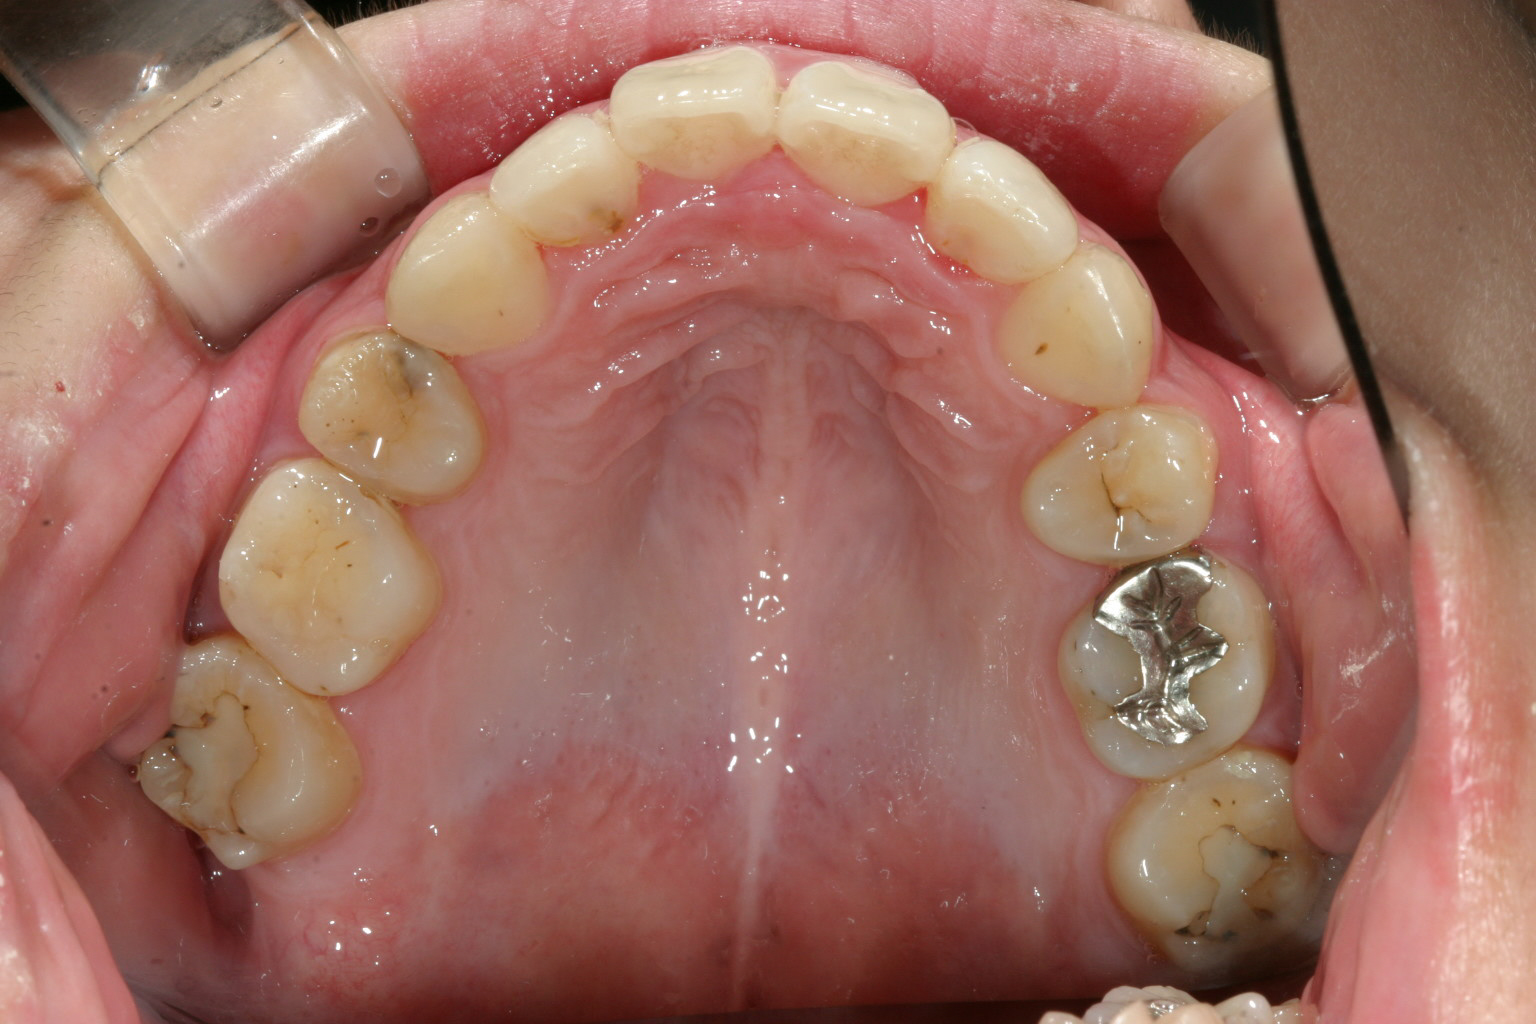

両サイドの小臼歯抜歯して前歯の出っ張りを中に入れました。

下顎は非抜歯です。アーチをU字に変えて綺麗に並んでます。

上下の出具合も抜群です。 加速矯正装置使用ですから期間も短縮されました。